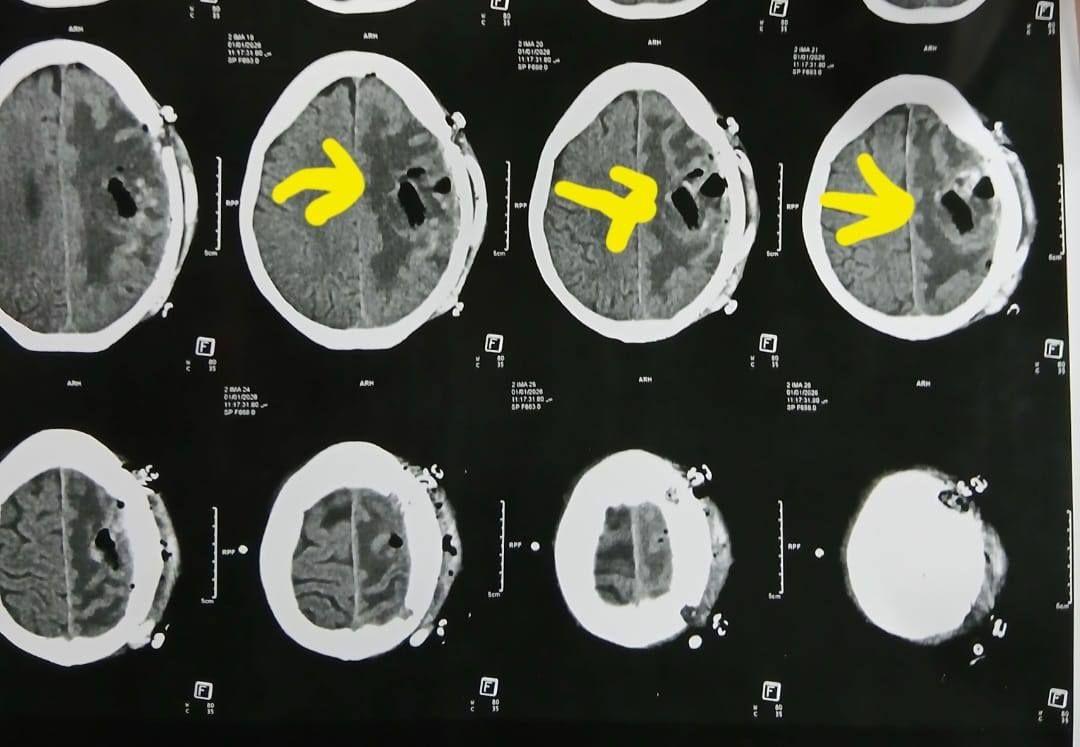

وكشف الدكتور إبراهيم الغريب رئيس قسم جراحة المخ والأعصاب بالمستشفى، أنه تعود تفاصيل الحالة إلى استقبال المستشفى المريضة بالعيادة الخارجية وهي تشكو من تنميل وضعف بالجانب الأيمن وثقل بسيط في الكلام، وبإجراء الفحوصات اللازمة من أشعة مقطعية ورنين مغناطيسي بالصبغة، تبين وجود ورم بالمخ، وتم إعطاؤها العلاج المناسب لحين استكمال الفحوصات.

أشعة المريضة

الأشعة الخاصة بالمريضة

الأشعة